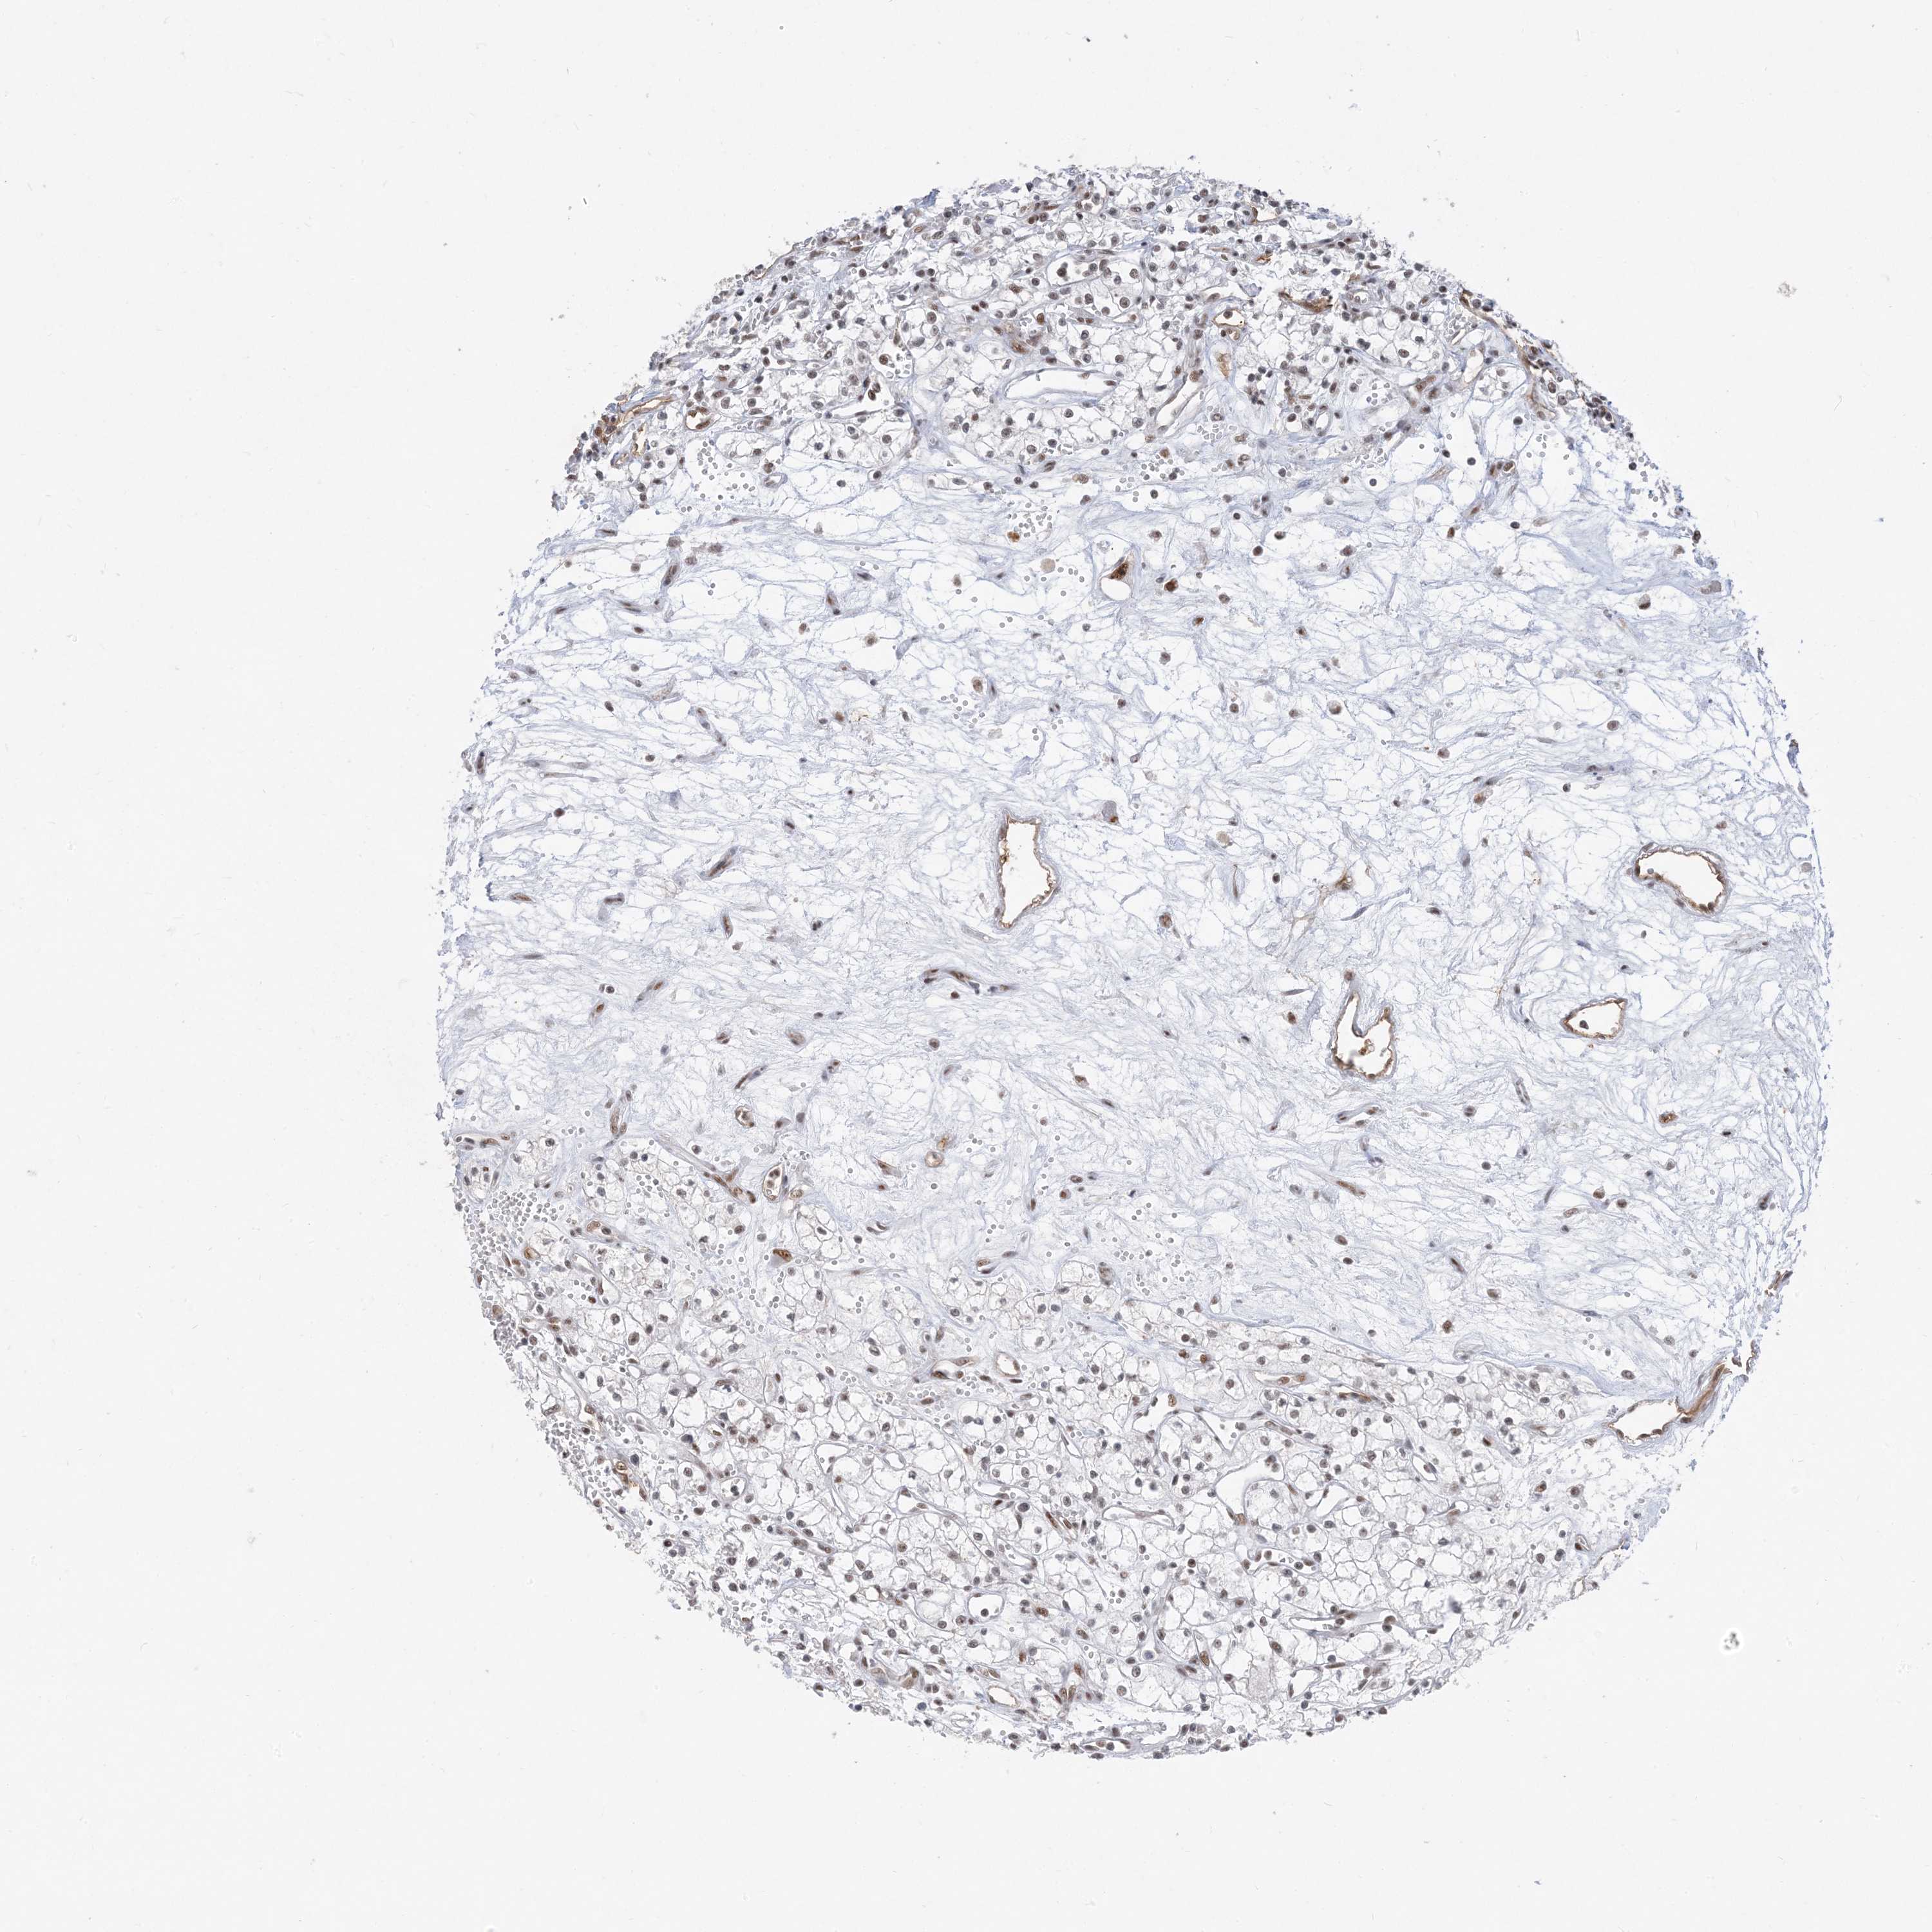

KIDNEY RENAL CLEAR CELL CARCINOMA (VALIDATION) - Interactive survival scatter ploti

The Survival Scatter plot shows the clinical status (i.e. dead or alive) for all individuals in the patient cohort, based on the same data that underlies the corresponding Kaplan-Meier plots. Patients that are alive at last time for follow-up are shown in blue and patients who have died during the study are shown in red.

The x-axis shows the expression levels (FPKM) of the investigated gene in the tumor tissue at the time of diagnosis. The y-axis shows the follow-up time after diagnosis (years). Both axes are complimented with kernel density curves demonstrating the data density over the axes. The top density plot shows the expression levels (FPKM) distribution among dead (red) and alive patients (blue). The right density plot shows the data density of the survived years of dead patients with high and low expression levels respectively, stratified using the cutoff indicated by the vertical dashed line through the Survival Scatter plot. This cutoff is automatically defined based on the FPKM cutoff that minimizes the p-score. The cutoff can be changed by dragging the vertical line or by entering a cutoff value in the square labeled "Current cut-off".

Under the Survival Scatter plot the p-score landscape (black curve; left axis) is shown together with dead median separation (red curve; right axis). Dead median separation is the difference in median mRNA expression between patients who have died with high and low expression, respectively. It is calculated as follows: median FPKM expression of dead patients with high expression - median FPKM expression of dead patients with low expression. This is intended to aid the user in visually exploring custom cutoffs and the associated p-scores and dead median separation.

Individual patient data is displayed and can be filtered by clicking on one or more of the category buttons on the top of the page. Categories describing expression level and patient information include: high, low, alive, dead, female, male and tumor stages. The scale of the x-axis can be toggled between linear and log-scale by clicking on the "x log" button. Mouse-over function shows TCGA ID, patient information and mRNA expression (FPKM) for each patient.

& Survival analysisi

Kaplan-Meier plots summarize results from analysis of correlation between mRNA expression level and patient survival. Patients were divided based on level of expression into one of the two groups "low" (under cut off) or "high" (over cut off). X-axis shows time for survival (years) and y-axis shows the probability of survival, where 1.0 corresponds to 100 percent.

SF3A3 is not prognostic in Kidney Renal Clear Cell Carcinoma (validation)

: 37.08

TCGA RNA samplesi

RNA-seq data is reported as average FPKM (number Fragments Per Kilobase of exon per Million reads), generated by the The Cancer Genome Atlas (TCGA) .

Normal distribution across the dataset is visualized with box plots, shown as median and 25th and 75th percentiles. Points are displayed as outliers if they are above or below 1.5 times the interquartile range. FPKM values of the individual samples are presented next to the box plot.

Average pTPM 35.4

Number of samples 100